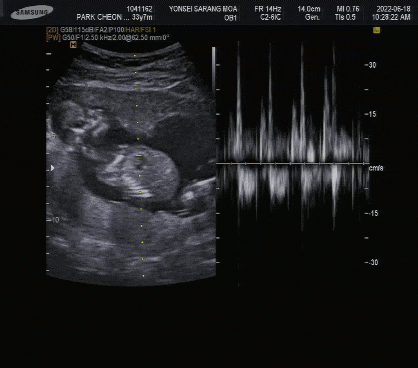

그리고 초음파 검사할 때 다리 사이를 봐야 하는 부분에서 원장님이 “엄마, 여기서 잠깐 고개를 돌려야 해.”라고 신호를 주셨어요.하하. 눈을 꼭 감고 있었는데 파티 끝나고 초음파 사진을 보니까 머리 크기 측정하고 다리 사이 재빨리 보고 허벅지 길이도 바로 측정하고…하하. 시어머니도 오셨는데 전혀 모르겠다고 하셨어요.하하.(시어머니는 이미 남자아이라고 확신하고 계셨어요.) 그리고 검사 후 외출하신 사이에 원장님이 쪽지에 성별을 적어서 봉투에 넣어서 주셨어요.집에 와서는 봉투를 서랍에 넣고 초음파 사진도 안 봤어요.하하.(남편이 엄청 궁금해 하셨는데 보여주지 않으셨어요.) 그러니까 호기심만 참으시면 됩니다.임신 16주 성별공개파티 후기